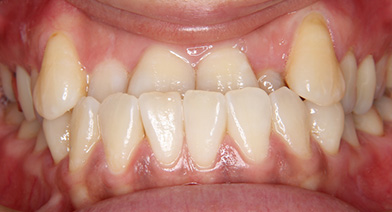

上顎前突、正中離開症例

- 主訴

- 出っ歯

- 診療名

- 上顎前歯部唇側傾斜、過蓋咬合

- 年齢・性別

- 10代男性

- 治療期間

- 2年8か月

- 治療費用

- 精密検査代:38,000円

装置代:720,000円

処置代:153,000円

保定装置代:40,000円

⇒総額:951,000円(税込み)

- 治療説明

- カリエールディスタライザーによる、上顎大臼歯の遠心移動、下顎位の前方適応を行った後、ワイヤーによる上顎前歯を後方移動しました。

今回のケースは、下顎が前方適応がうまくいくかがポイントでした。この患者様は、前歯の早期接触があり、下顎がかみ込むと後方に下がるため、下顎が前方適応すると見込んで治療を開始しました。ケースによっては、小臼歯抜歯、外科矯正となることもあります。抜歯:上顎両側8番

治療装置:カリエールディスタライザー、マルチブラケット装置

固定装置:なし

リテーナー:クリアリテーナータイプ

- リスク・副作用

- 痛み・治療後の後戻り・歯根吸収・歯髄壊死・歯肉退縮